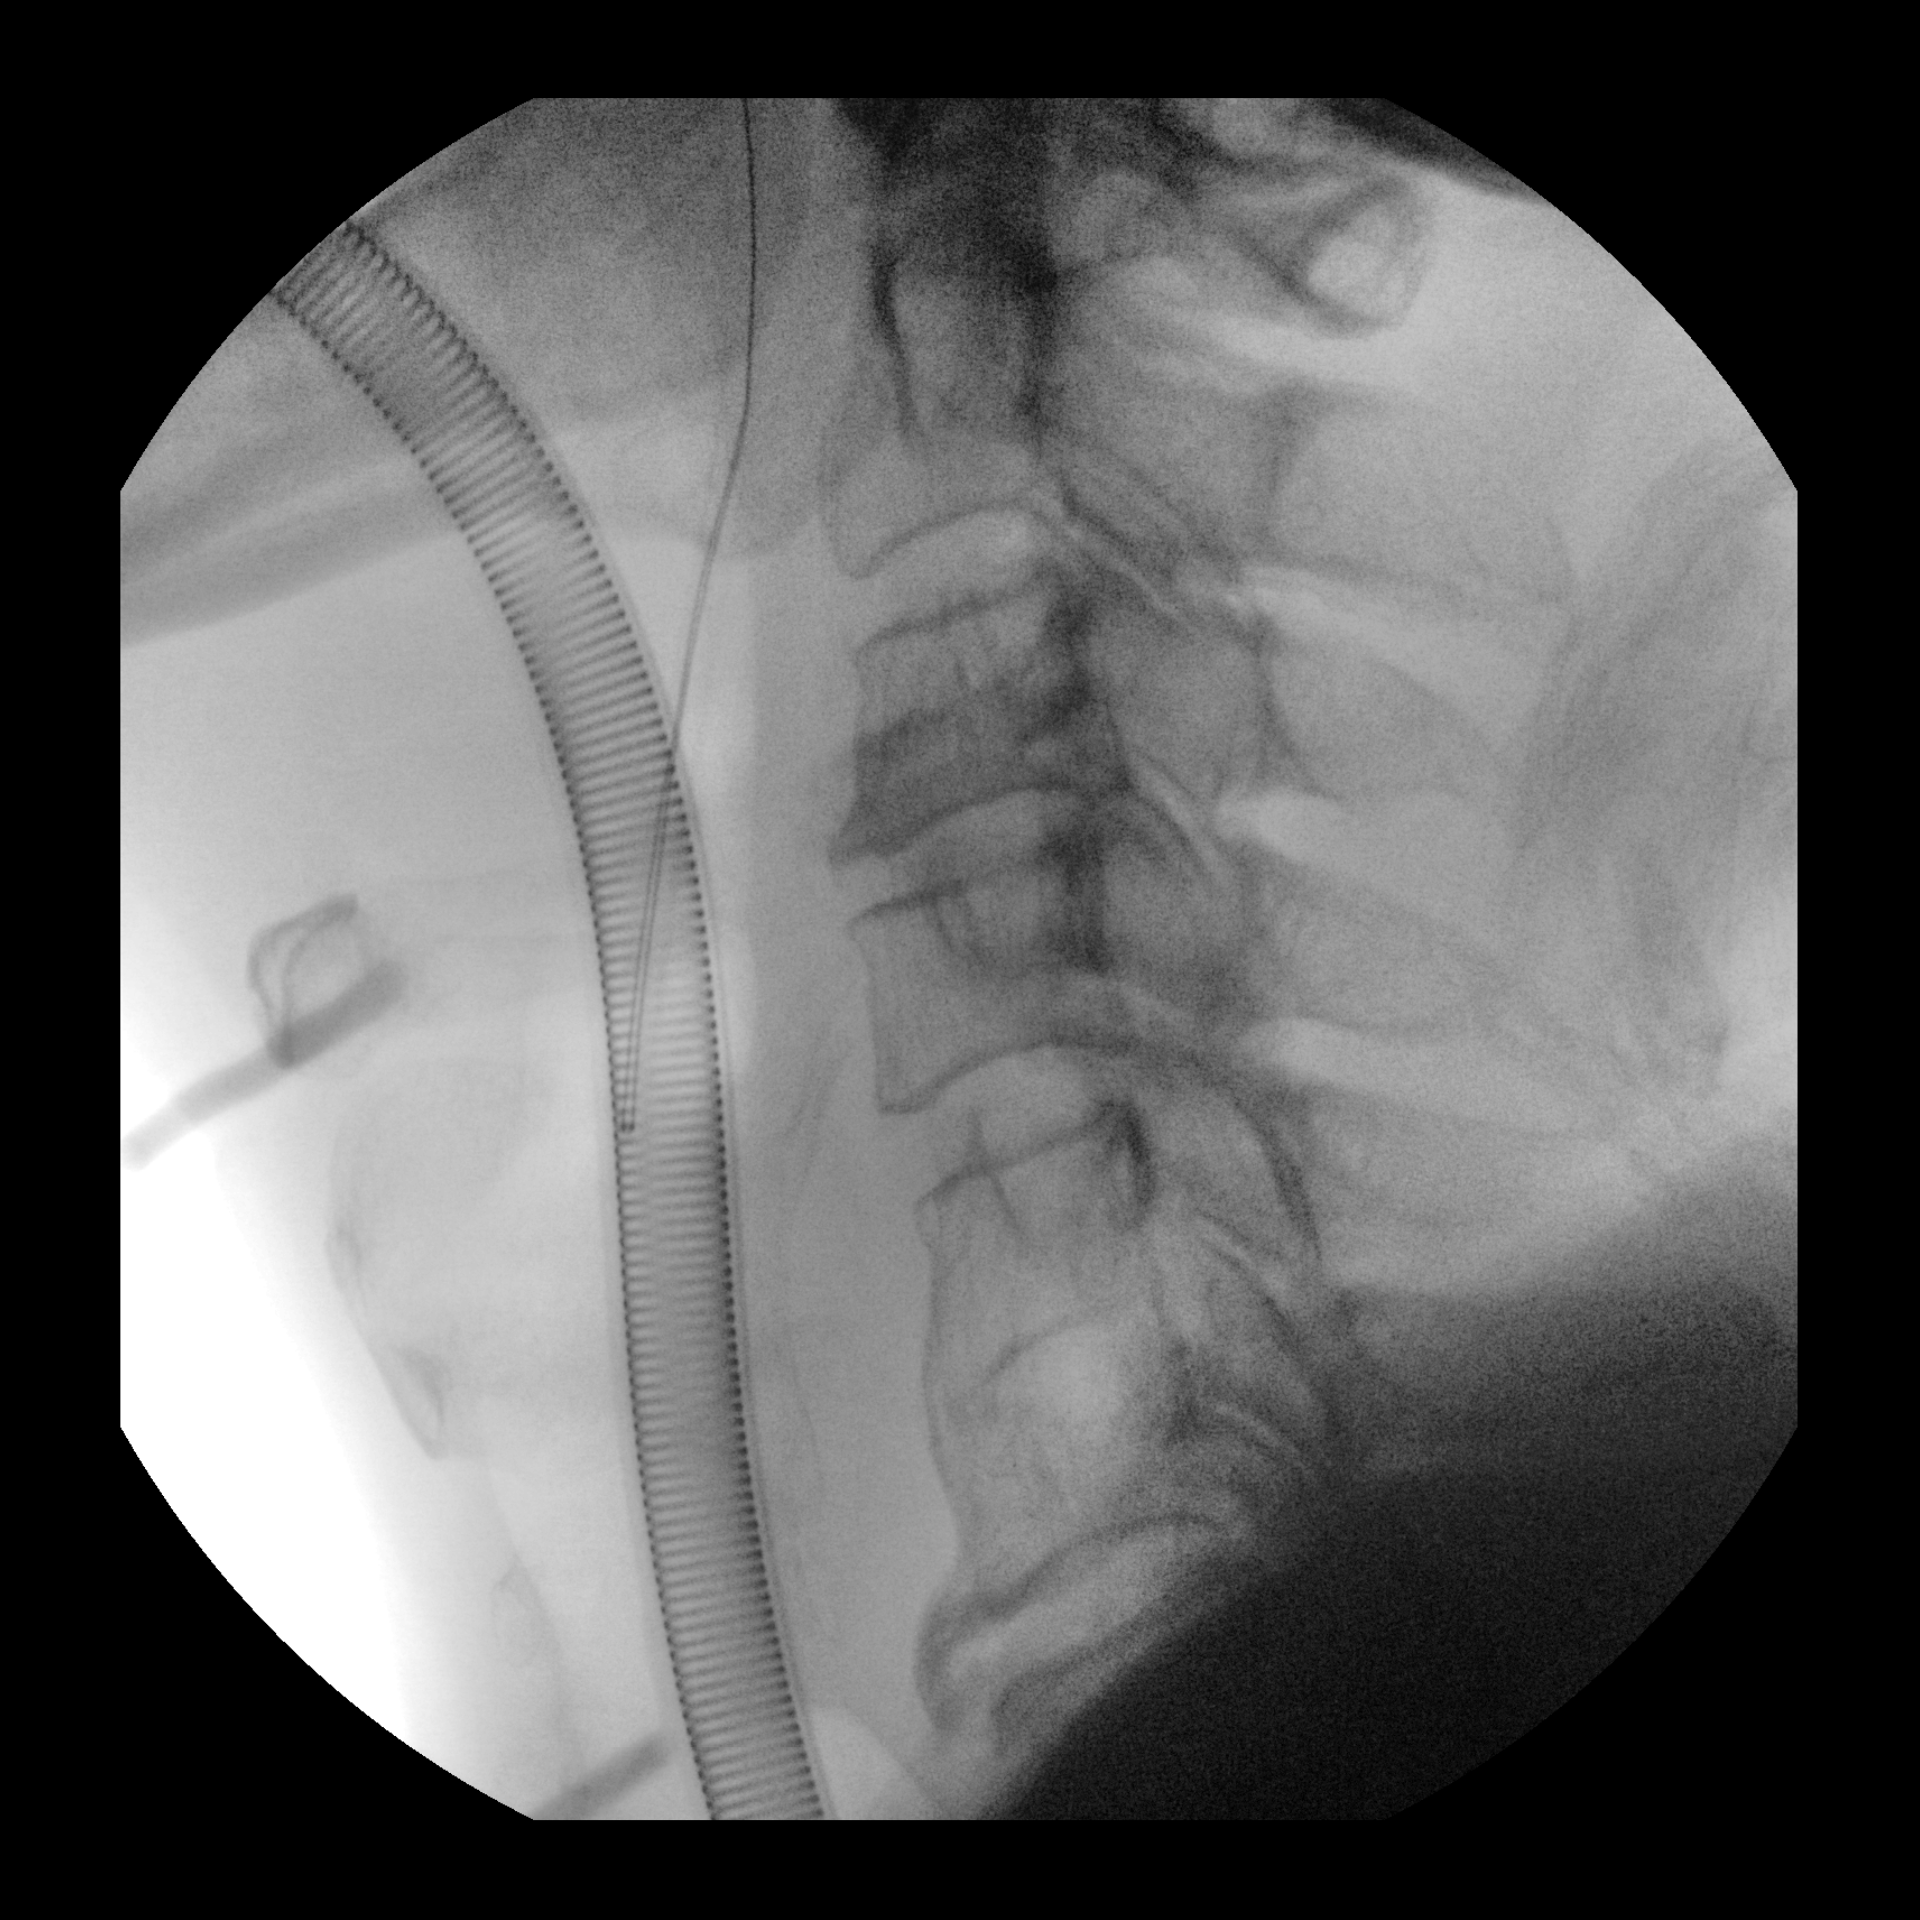

Stunning Image Quality / Detailed point-and-shoot imaging

- 1:1 image detail with 21 cm CMOS flat panel detector (CFD).

- 1.5k x 1.5k processing size.

- 4K 27” UHD Monitor Display.

- 30 cm (11.8”) Squircle images – See more anatomy.

- Advanced image chain softwares – See more clearly with automatic motion correction.